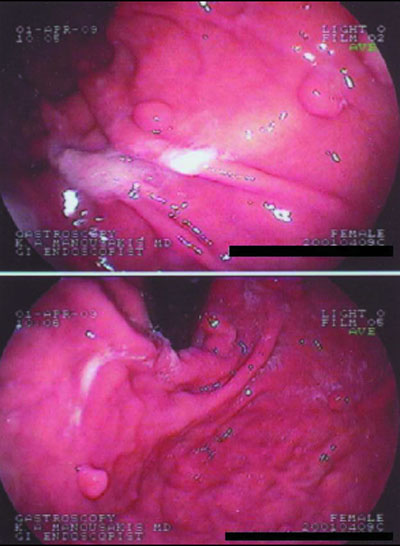

Ασθενής με κοιλιακό άλγος, ίκτερο και αυξημένα χολοστατικά ένζυμα. Προ εβδομάδος υποβλήθηκε σε λαπαροσκοπική χολοκυστεκτομή.

3. Παρά την προηγηθείσα χολοκυστεκτομή, το μεγαλύτερο μέρος της χοληδόχου κύστης βρίσκεται στη θέσης της και περιέχει μεγάλο χολόλιθο (προϋπήρχε δίλοβος χοληδόχος κύστη ;). Επίσης, υπάρχει διαφυγή σκιαγραφικού από το κολόβωμα.